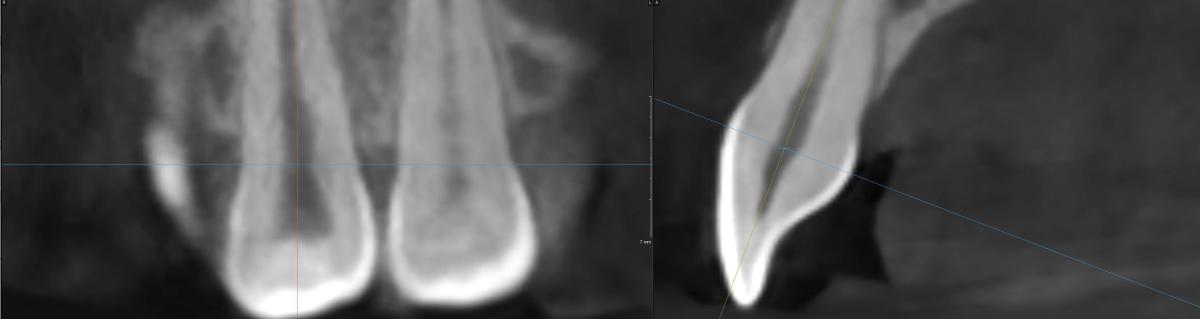

Вчера сделала КТ.

Юрий Жигурт, Подскажите, пожалуйста, есть ли кариес на 11 зубе (сторона контактная с 12 зубом)? Или его признаки. Если да, то насколько глубоко? Если возможно покажите, пожалуйста, стрелочкой где это наблюдается. Спасибо!

anastasiiia, есть основания предполагать: